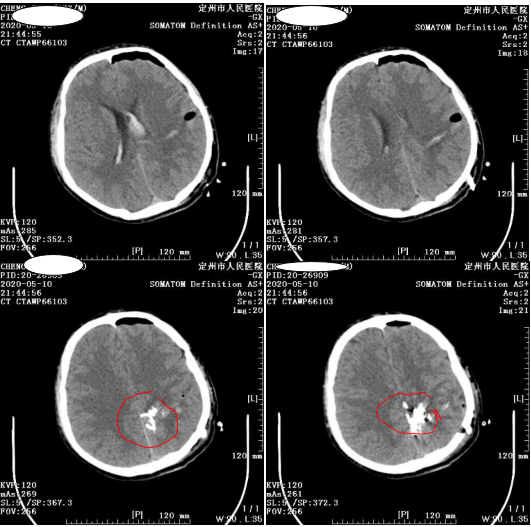

向家属再次交代病情和治疗方案后手术继续,肖主任熟练地将一个细小的导管送入靠近畸形团的动脉里,

向里面缓慢注射

OYNX18的胶状栓塞剂,打完一支胶后,畸形团缩小,但仍有残留。

打入两支OYNX18胶后小雷颅内畸形团稍有残留。如果继续打胶有可能栓塞正常血管。

肖主任决定将小雷转入手术室行开颅血肿清除术。手术全程出血约200ml,小雷生命体征平稳。

高密度影为胶水显影

术后,小雷神志清楚,语言流利,右下肢肌力1级,左侧肢体肌力5级,复查头颅CT显示血肿基本清除

。